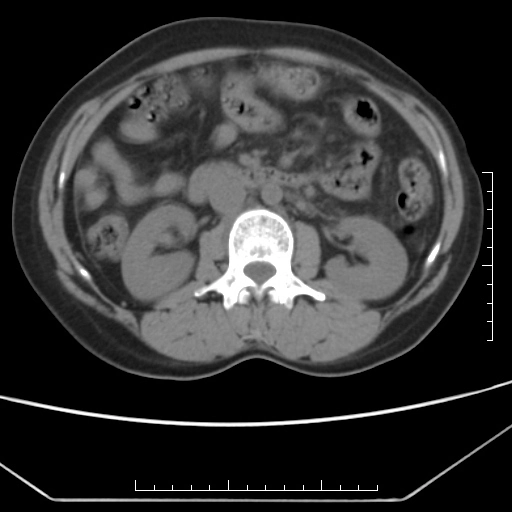

• Tăng áp lực tĩnh mạch cửa (Portal Hypertension)

• Thay đổi đậm độ gan thoáng qua trên CT (Transient hepatic attenuation differences - THADs)

• Huyết khối tĩnh mạch cửa (Portal vein thrombosis - PVT)